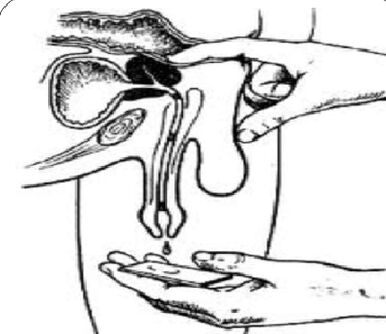

Der Prozess der transrektalen digitalen Untersuchung wird mit der Sammlung von Drüsensekreten kombiniert. Manchmal ist es notwendig, das Sekret aus jedem Lappen separat zu entnehmen.

Der „Goldstandard“ bei der Diagnose einer chronischen Prostatitis sind:

- Sammeln der ersten Urinportion.

- Sammlung der zweiten Urinportion.

- Gewinnung von Drüsensekreten durch Massage.

- Sammlung der dritten Urinportion.

Anschließend erfolgt eine mikroskopische und bakteriologische Untersuchung des Materials.